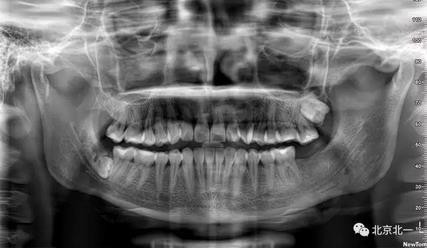

圖十二:拍片確認無誤。

術后第二天,右側面部稍有腫脹,撤引流條拍攝正面照片。歡迎同行 探討一下什么是微創拔牙。

總結:單純拍片看牙齒并不復雜, 通過微創拔牙有絲分裂可以避免傷及神經, 本病例特殊之處在于牙齒顏色和骨顏色無法區別。導致去骨或者分牙比較茫然, 不可大意,以及磨牙的手感和去骨的手感一致時,兩者不好區分。 只能偏向保守, 多角度拍片再三確認后予以安全拔除。 另外CBCT模式上看智齒位置也有誤差,醫師要根據經驗調整,特別是在這種哪里是骨,哪里是牙的情況,不能盲目大范圍去骨導致術中骨折。

另外重點:強調無菌,注意不要污染手術,位置深,創傷大,完全是一個口腔頜面部手術, 按照外科原則準備。 該病例手術后口服消炎藥,并沒有輸液抗炎。 腫脹不明顯和書中完全無菌操作, 用生理鹽水冷卻的專用種植機分牙,拒絕管路水污染, 無敲擊以及術后引流片引流有很大關系。